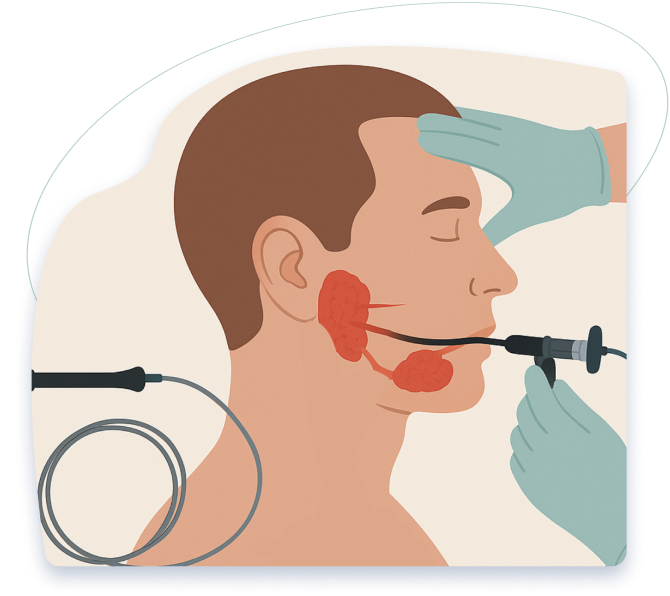

Sialendoscopy

Minimally invasive endoscopic treatment for blocked salivary glands and stones without external scarring or gland removal. Using ultra-thin endoscopes, we directly treat blockages within salivary ducts, enabling same-day treatment, preserved function, minimal discomfort, and excellent long-term relief.